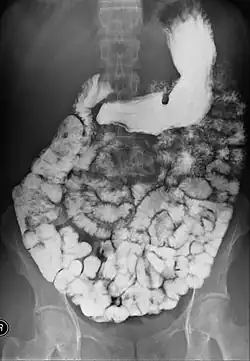

Transit baryté, visualisation de l'intestin grêle.

Un transit baryté est un examen radiologique permettant d'étudier le tube digestif haut : œsophage, estomac, duodénum et intestin grêle[1]. Il consiste à faire ingérer par un patient de la baryte, un produit de contraste opaque aux rayons X. Puis des clichés radiographiques sont pris à différents temps, permettant d'explorer l'ensemble du tractus digestif haut à mesure que celui-ci se remplit de baryte.

Cet examen permet de dépister des anomalies telles que tumeurs, polypes, diverticules, inflammation et infection.